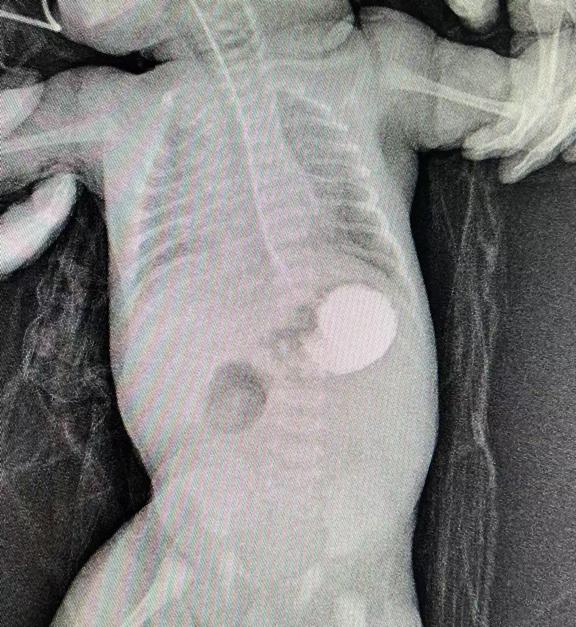

術(shù)后復(fù)查十二指腸已通暢

次日,在新生兒科、麻醉科及手術(shù)室的密切配合下,患兒在全麻下由上海兒童醫(yī)學(xué)中心(國家兒童醫(yī)學(xué)中心)小兒外科陳杰教授指導(dǎo),衡陽市中心醫(yī)院小兒外科唐水平主任進(jìn)行剖腹探查,術(shù)中發(fā)現(xiàn)環(huán)狀胰腺引起的十二指腸閉鎖梗阻,行十二指腸菱型吻合術(shù)+空腸營養(yǎng)管留置,手術(shù)歷時(shí)兩小時(shí)后順利完成,手術(shù)結(jié)束后即脫機(jī)拔管。